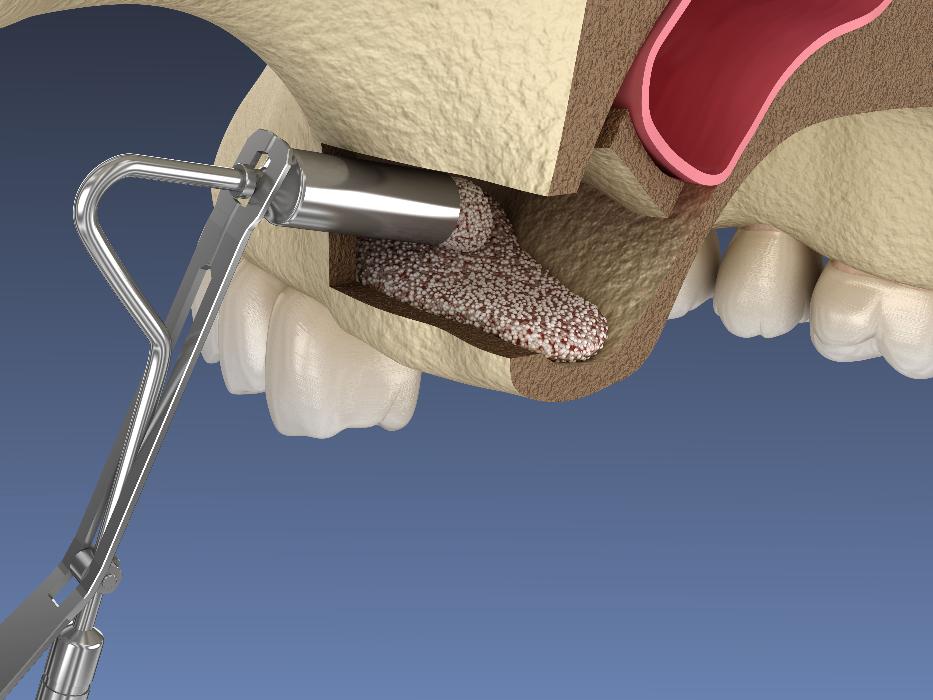

Sinus Lifts

When there is insufficient bone height in the upper jaw for dental implants, we may recommend a sinus lift. This procedure involves lifting the sinus membrane and adding bone graft material to create a solid foundation for implants. Sinus lifts enable patients with bone loss to receive successful dental implant treatment, restoring their ability to chew, speak and smile with confidence.

A sinus lift, or sinus augmentation, adds bone to the upper jaw, raising the sinus floor to allow for additional bone. Dr Skaf may recommend a sinus lift if the sinus location or height inhibits the successful